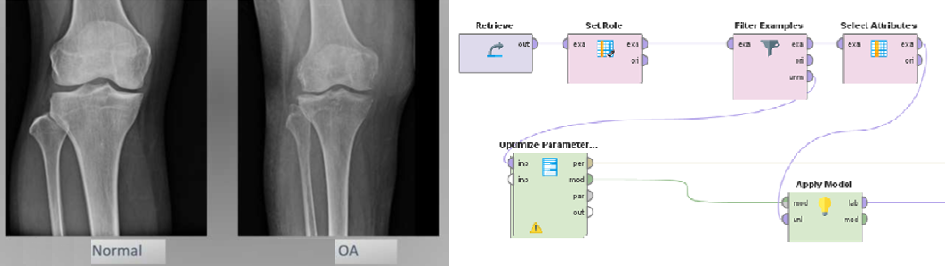

• 以 RapidMiner 建立 AI 預測模型,可預測未來2年與3年的關節惡化情況。

• 使用 RapidMiner 與 Naive Bayes 方法建立預測模型,預測退化性關節炎的病況進程。

• 根據驗證結果,模型預測未來2年與3年的病情變化準確度達8成。